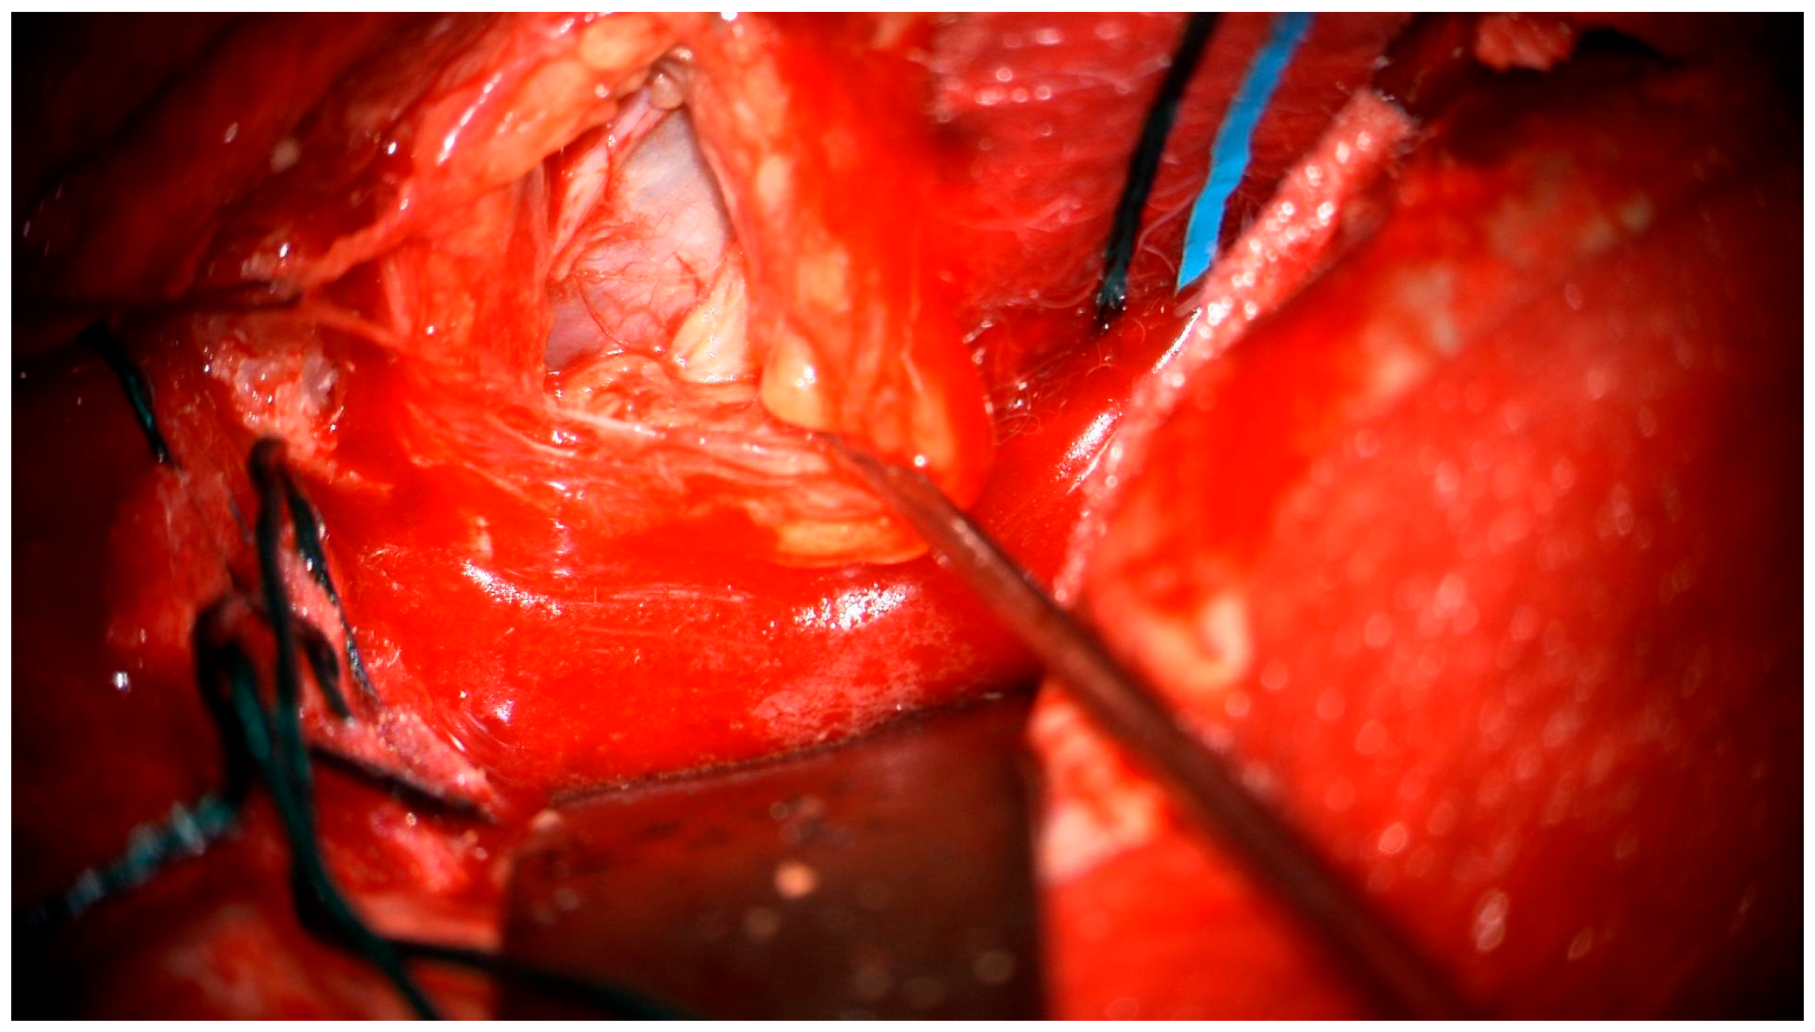

After the lumbar drainage was inserted, the patient was positioned in a supine position, with the head fixated in a Mayfield clamp and turned to the right. Neuronavigation based on previous MRI was used to mark the incision. A left-sided pterional craniotomy was performed to access the eye socket; a resection of part of the superior orbital wall was performed. With a surgical microscope, the intraorbital dura mater was opened. The pathological tissues appeared in a light gray color, tissues were loose, and the tumor was fragmented and aspirated with the help of a CUSA (cavitronic ultrasonic surgical aspirator) (Figure 5). After closure of the dura mater, the orbital wall was reconstrued with an individually mended standard titan orbital wall implant, which was fixated with three mini screws. Under the microscope, pathological tissues in the medial brain fossa were visualized and resected subtotally.

Figure 5. Surgical microscope view of the surgical site.